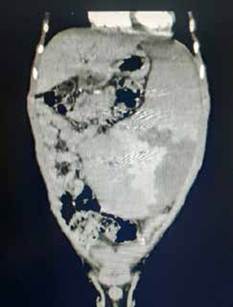

Paciente masculino de 16 años, residente en Bogotá, quien consultó por dolor abdominal súbito severo, sin antecedentes médicos o quirúrgicos previos, salvo consumo crónico de marihuana. Se llevó a laparotomía diagnostica por el servicio de cirugía general, encontrando varices congestivas en los compartimentos supra e infra meso cólico, con varices en todo el omento mayor y menor, pero sin sangrado activo (figura 2), e hígado de características normales. Debido a los hallazgos, no se realizó ningún procedimiento adicional.